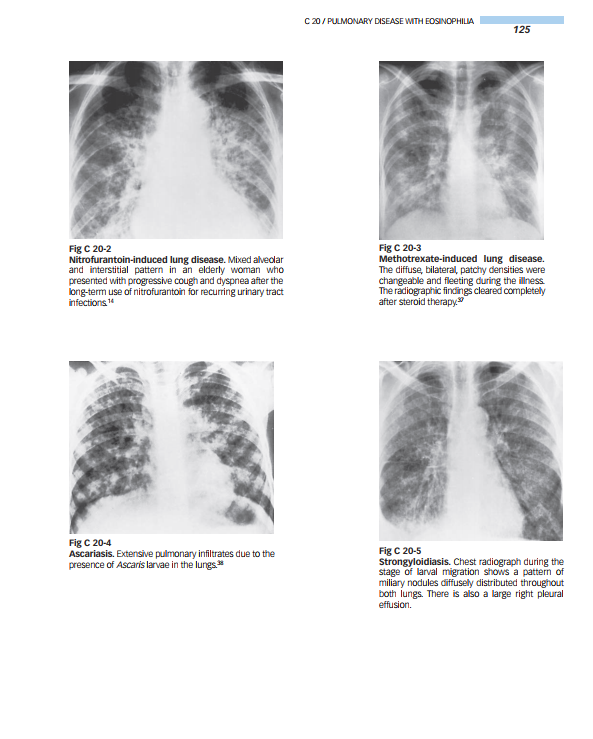

Organized by anatomic area, the book outlines and illustrates typical radiologic findings for every disease in every organ system. Tables on the left-hand pages outline conditions and characteristic imaging findings…and offer comments to guide diagnosis. Images on the right-hand pages illustrate the major findings noted in the tables.